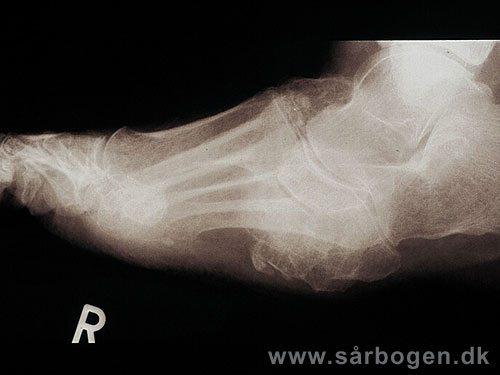

Charcot i ankel (rtg...

Zoom